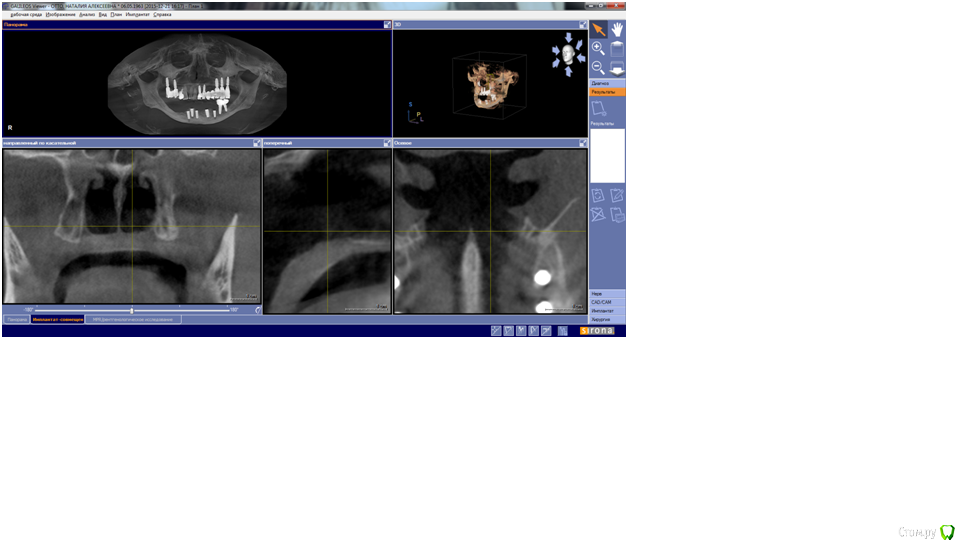

Nataly07 Опубликовано 7 января, 2016 Поделиться Опубликовано 7 января, 2016 Уважаемые доктора, была бы очень благодарна вам, если бы нашли время ответить на очень важный для меня вопрос. В начале декабря 2015 была проведена операция по имплантации на нижней челюсти. Были установлены 5 имплантатов. После операции выяснилось, что с левой стороны присутствует онемение подбородка. Была сделана КТ. Хирург посмотрел снимок и сказал, что всё нормально, имплантат не касается нерва. В заключении врача-рентгенолога написано: имплантат 3.5 – апикальная треть перфорирует нижнечелюстной канал на всем протяжении в области ментального отверстия. Ниже имплантата с оральной стороны визуализируется дефект оральной компактной пластинки. В переводе с медицинского на общечеловеческий язык, что это означает и каковы должны быть дальнейшие действия?Имплантат 4.3 – ниже имплантата визуализируется сквозной дефект нижней компактной пластинки. Имплантат надо удалять? Какие могут быть последствия, если его не удалять?Снимки сделаны в программе Галилео, не знаю, как их сохранить. Ссылка на комментарий

Nataly07 Опубликовано 8 января, 2016 Автор Поделиться Опубликовано 8 января, 2016 то есть 3.5 можно и не убирать? рентгенолог написал в заключении, что он перфорирует нижнечелюстной канал в области ментального отверстия, а ниже имплантата с оральной стороны визуализируется дефект оральной компактной пластинки - что это такое? С этим можно жить?) а между имплантатами 4.3 и 4.2 расстояние 1,5 миллиметра, как вы считаете, смогут они прижиться? не нарушится ли питание кости и не придется ли их потом убрать оба? ниже имплантата 4.3 - сквозной дефект нижней компактной пластинки. Такой имплантат можно сохранять? 4.1 - оголение в вестибулярной стенке коронковой трети имплантата до 4,8 миллиметров, сможет ли он в дальнейшем послужить опорой для коронки? Планируется протезирование на винтах. Ссылка на комментарий

IvanK Опубликовано 9 января, 2016 Поделиться Опубликовано 9 января, 2016 Не надо постоянно писать одно и тоже, все понятно было сразу Имплантат, который является причиной онемения - убрать Сделать фото в полости рта, выложить сюда Сходить к ортопеду, который Планируется протезирование на винтах. и показать снимки, послушать его мнение 1 Ссылка на комментарий